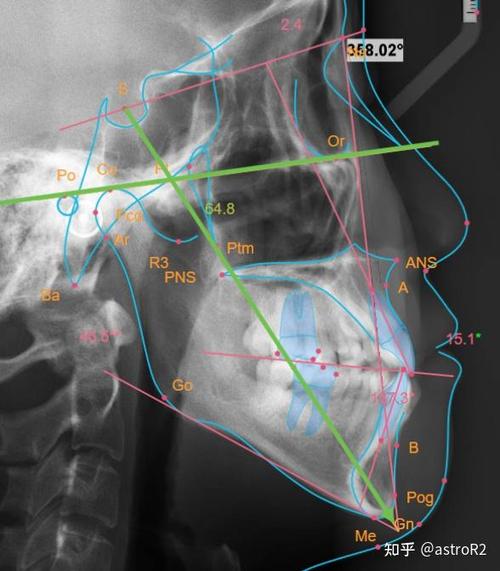

头影测量的基础是头颅定位仪的标准化使用,确保拍摄时患者颅部与X线球管的位置固定,消除因头部倾斜导致的误差,常用标志点包括颅底点(S)、鼻根点(N)、蝶鞍点(Sella)、上齿槽座点(A)、下齿槽座点(B)等,这些标志点的连线构成重要参考平面,如SN平面(由S和N连线构成,代表颅底基准)、FH平面(由眶下缘与耳点连线构成,代表眶耳平面)、MP平面(下颌下缘切线,代表下颌平面),通过测量这些平面间的角度和距离,可量化分析颌骨矢状向(如上下颌骨前后位置关系)、垂直向(如面部高度比例)及水平向(如宽度协调性)的异常。

美国正畸临床中,头影测量指标可分为骨骼、牙齿及软组织三大类,骨骼指标中,SNA角反映上颌骨相对于颅底的位置,正常值约82°±3°,SNA角增大提示上颌前突,减小提示上颌后缩;SNB角反映下颌骨相对于颅底的位置,正常值约80°±3°,SNB角增大提示下颌前突,减小提示下颌后缩;ANB角则综合评估上下颌骨的矢状关系,正常值2°±2°,正值Ⅲ类骨面型,负值Ⅱ类骨面型,垂直向指标如前面高(N-Me)与后面高(S-Go)的比值(正常值约62%~65%),可判断面部垂直比例是否协调,过大或过小可能导致“长面型”或“短面型”畸形,牙齿指标包括上中切牙凸距(U1-APg,正常值2~4mm)、下中切牙斜度(L1-MP,正常值95°±5°),用于评估牙齿唇倾度及与基骨的关系,避免治疗中牙根吸收或唇侧骨开窗,软组织指标如鼻唇角(鼻小柱与上唇交角,正常值90°~100°)、软组织颏前点(Pos-Pog)距离,直接关联患者面部美观,是制定正畸-正颌联合治疗的重要参考。

美国正畸头影测量的应用流程严谨规范:首先拍摄头颅侧位片及曲面断层片,通过数字化软件(如Dolphin Imaging、OnyxCeph)进行标志点定位与自动测量,生成测量报告;结合患者临床检查(口内咬合关系、面部对称性、关节功能)及模型分析,综合判断错畸形的病因机制;针对骨性畸形,通过生长改良(如功能性矫治器)、掩饰性治疗(拔牙代偿)或正颌手术制定方案;针对牙性畸形,确定拔牙模式、支抗设计及牙齿移动计划,对于ANB角>5°的Ⅱ类1分类错,若患者处于生长发育高峰期,可采用头帽式口外弓抑制上颌生长;若成年患者拒绝手术,则通过拔除上颌第一前磨牙,内收上前牙、压低下前牙改善矢状关系。